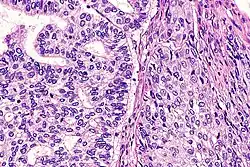

| Micrograph of an adenosquamous carcinoma of the lung. The adeno- or glandular component is on the left of the image and the squamous component on the right of the image. H&E stain. | |

Light microscopy shows a combination of gland-like cells and squamous epithelial cells.[4] On immunohistochemistry, it is typically positive for CK5/6, CK7 and p63, and negative for CK20, p16 and p53. On genetic testing, KRAS and p53 are typically altered.[4]